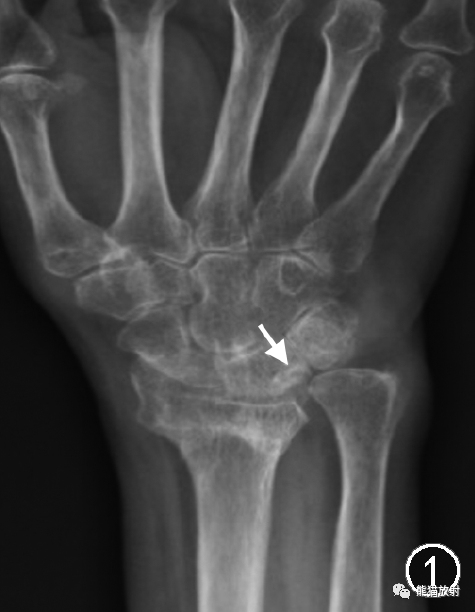

标准后前位(肩关节外展90°、肘关节屈曲90°、腕关节中立位)X线摄片的典型表现包括尺骨正向变异,偶尔可见尺骨中性变异或尺骨负向变异,以及导致尺骨相对过长或桡骨远端背倾程度增加的其他因素,例如桡骨远端骨折的畸形愈合(图1);月骨近端尺侧面、三角骨近端桡侧面及尺骨头关节面硬化和软骨下囊变(图1,2)。

图1 继发于桡骨远端骨折畸形愈合的尺骨撞击综合征。女,66岁,右侧桡骨远端骨折愈合后右腕关节疼痛。腕关节X线正位片示桡骨远端骨折畸形愈合,继发尺骨相对过长、尺骨正向变异,月骨近端尺侧面骨质硬化改变(↑)